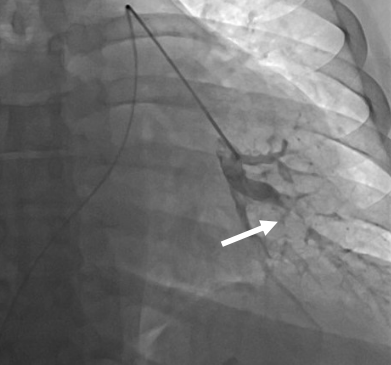

在征得患者同意之后,张主任先行选择性肺动脉造影,发现患者双肺动脉均存在弥漫性血栓(图2),测量肺小动脉楔压50/,显著高于正常,继而将导管通过卵圆孔未闭测量左心房压力为34/,同样显著高于正常。于是张主任毅然决定,先行卵圆孔未闭球囊扩张术(图3)减轻左心室前负荷,防止左心功能恶化,继而行肺栓塞球囊扩张术解除肺动脉梗阻。手术非常顺利,患者病情显著好转,术后当日晚上即可平卧,继而双下肢水肿消失,术后一个月患者日常活动毫无压力,心脏超声发现左心室射血分数自30%上升至46.6%。

(图2)选择性肺动脉造影显示,左下肺动脉因肺栓塞而几乎完全闭塞。